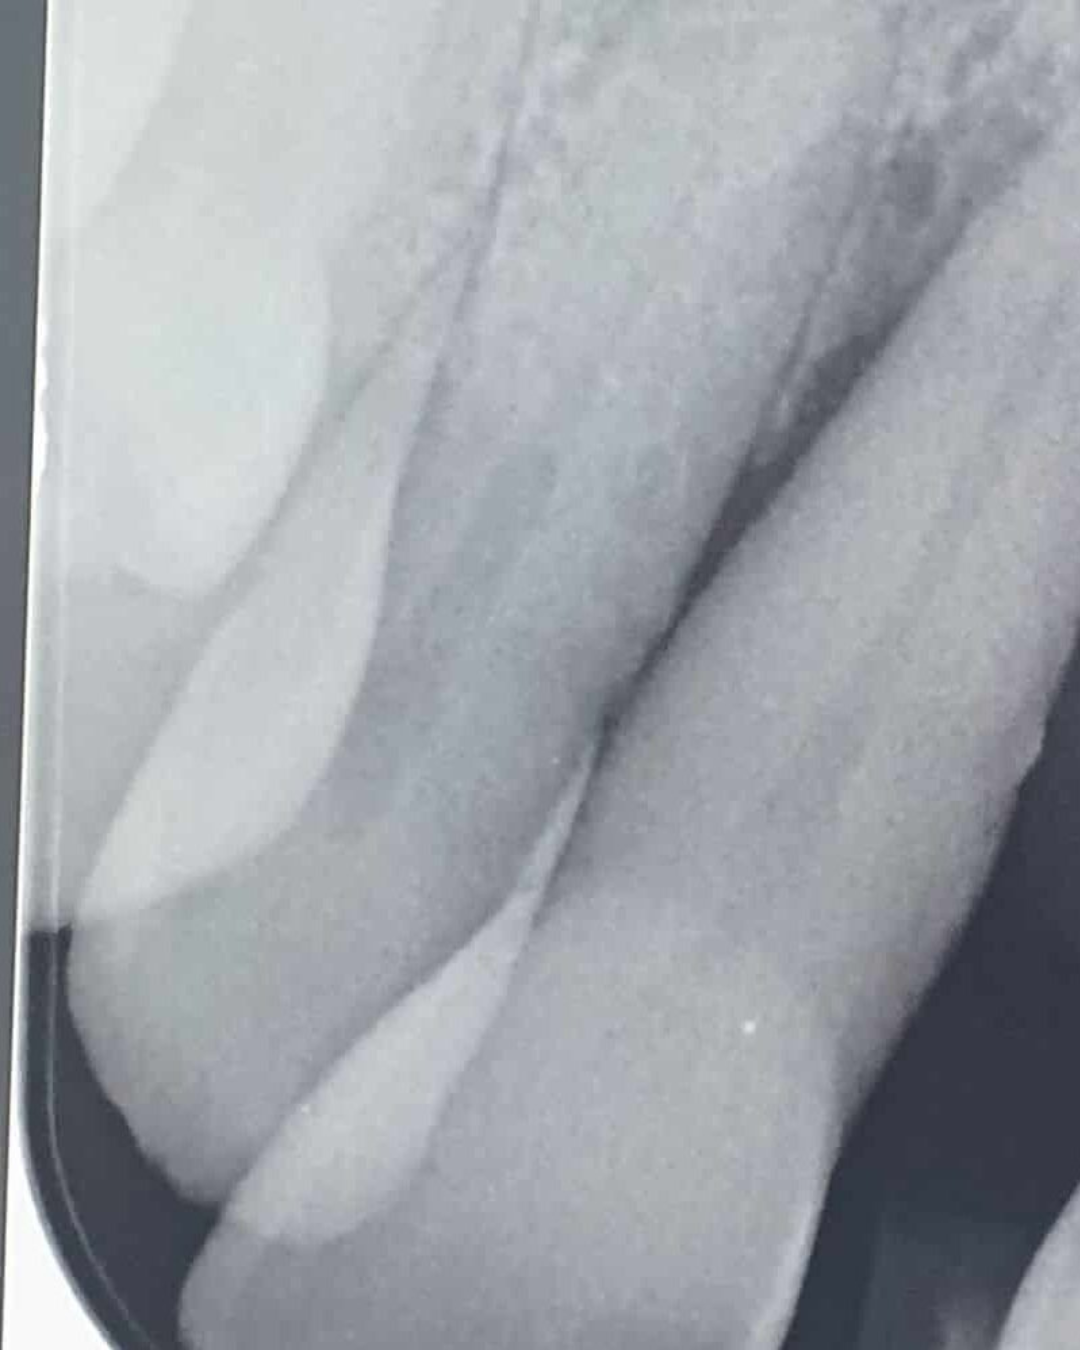

Within Dentistry, there have always been certain surgical procedures, such as the extraction of impacted wisdom teeth, that carry a small risk of post operative complications. Patients will have been made aware of these risks should they present. However, with more recent advances in technology and the use of 3-dimensional CBCT scanning, we can minimise these risks even further. In fact, some of these risks can be totally eliminated by utilising this technology in the planning and treatment stages. It is a great tribute to modern dentistry that we are striving for safety and success rates edging ever closer to the 100% mark. This is largely due to the utilisation of digital technology within dentistry.

We are proud to be using these latest protocols at our clinic.